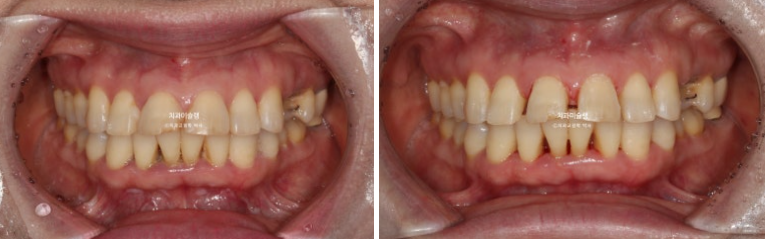

첫세트 장치 14개를 다 낀 후 모습입니다.

25년 1월 장치를 낀지 4개월 후 모습입니다.

앞니 사이 틈은 상당히 줄었고

임플란트 할 공간도 적절히 조절합니다.

미진한 부분을 더 개선하고자 추가장치 제작에 들어갑니다.

이제 전후 비교해보겠습니다.

앞니 각도의 개선이 눈에 띕니다.